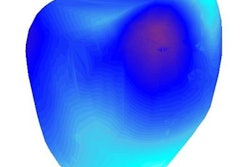

Overview of the registration techniques used in FEM. The post-treatment bladder, prostate, and rectum are shown in green, blue, and pink, respectively. Pretreatment surfaces are shown in gray. Quantitative measurements reflecting changes can be used to track treatment response over time. Image republished with permission of PLOS One, from Robert Toth, Dan Sperling, Anant Madabhushi: http://dx.doi.org/10.1371/journal.pone.0150016.Before and after

The FEM technique appeared to accurately assess the bladder and rectum deformations, the authors wrote. The results also suggest that laser treatment causes a decrease in prostate volume, which appears to manifest predominantly at the site of ablation.

After aligning the images spatially, changes to MRI intensity values can be seen clearly at the ablation site.